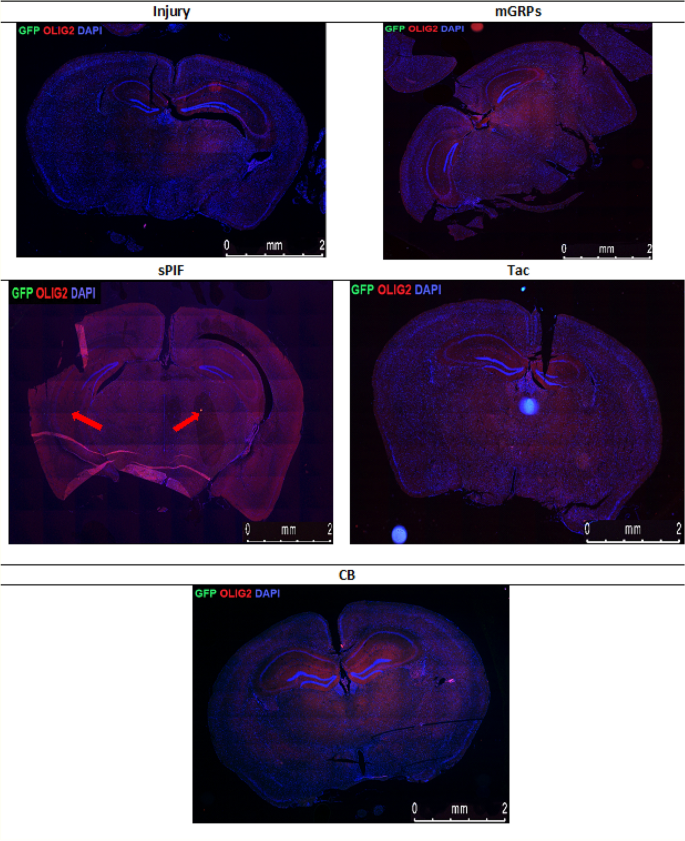

mGRPs progeny in brain parenchyma: representative immunofluorescence images of oligodendrocytes (OLIG2 + red marker) and mGRPs (GFP + green marker) in the diencephalon on day 56. Green arrows indicate positive cells in the sPIF group. mGRPs: glial-restricted precursors; sPIF: synthetic preimplantation factor; Tac: Tacrolimus, CB: co-stimulatory blockade.

Immunofluorescence staining of mGRP cells (GFP + green marker) and oligodendrocytes (OLIG2 + red marker) on whole cross section of the mouse diencephalon in the study groups. There can be seen a larger area of oligodendrocytes in the group with sPIF administration (indicated by red arrows). mGRPs: glial-restricted precursors; sPIF: synthetic PreImplantation Factor; Tac: Tacrolimus, CB: co-stimulatory blockade.